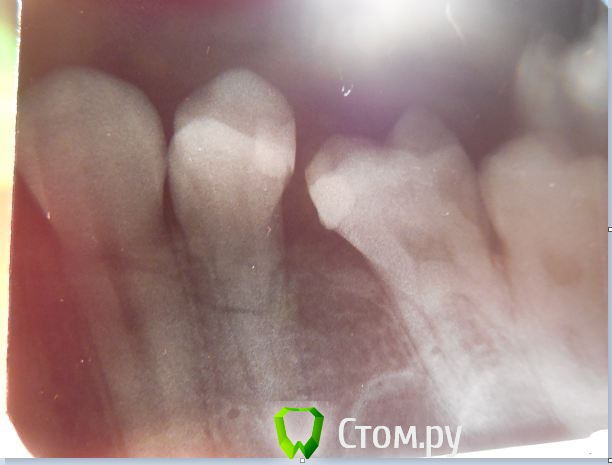

a_b Опубликовано 25 июня, 2014 Поделиться Опубликовано 25 июня, 2014 Добрый вечер!Очень нужен совет. Получила удар копытом в челюсть - около месяца не могла попасть к стоматологу, не открывался рот. Сейчас обнаружилось, что сломан корень 14го зуба. Врач предлагает удалять, но у меня уже давно нет соседнего зуба (15), очень пугает перспектива остаться с зияющей пустотой http://forum.stomatologija.su/public/style_emoticons/default/sad.pngЗуб сначала сильно шатался, от малейшего прикосновения возникала резкая боль. Сейчас почти не качается, не беспокоит. Боль возникает только при надавливании сверху.Собственно, вопросы:1. есть ли хоть какая-то возможность сохранить зуб? Нашла клинику, которая пишет на сайте, что они сохраняют зубы со сломанным корнем и как-то решают проблему. Такое возможно или это просто реклама?2. если удаление неизбежно, то какие существуют временные варианты закрыть дыру? Очень скоро предстоят важные собеседования, отсутствие переднего зуба очень пугает.3. возможно ли просто не трогать зуб 3-4 недели или это опасно? Сейчас зуб не беспокоит, ем на другую сторону.Заранее прошу прощения, если вопросы не совсем корректно заданы, впервые столкнулась с такой проблемой и даже не знаю, к какому специалисту идти на консультацию.Через полторы недели надолго уезжаю из Москвы, нужно срочно что-то решать, а я в полнейшей растерянности http://forum.stomatologija.su/public/style_emoticons/default/sad.png Буду очень благодарна, если кто-то найдет время откликнуться! Ссылка на комментарий

diesel87 Опубликовано 25 июня, 2014 Поделиться Опубликовано 25 июня, 2014 Здравствуйте, от удара копытом сломался только корень 14 зуба? И все? Челюстные кости все целы? По поводу зуба, он уже не жилец, не спасти его ни чем, разве что продлить мучения, удаляйте. Закрыть можно временным или постоянным мостом, сходите на консультацию к хирургу и ортопеду. 4 Ссылка на комментарий